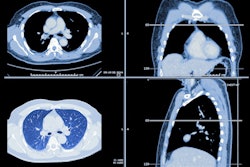

CT lung cancer screening reduces the risk of death from lung cancer, according to a new meta-analysis that combines data from all randomized controlled trials performed so far. In fact, CT lung screening compares favorably with breast screening, researchers reported in the November edition of the Annals of Family Medicine.

In an analysis of eight randomized controlled trials (RCTs) that covered over 90,000 individuals, CT lung cancer screening produced a relative risk reduction of 0.81 for death from lung cancer and an absolute risk reduction of 0.4%, both numbers that were statistically significant. On the other hand, screening did not reduce all-cause mortality to a statistically significant degree (Annals of Family Medicine, November 2020, Vol. 18:6, pp. 545-552).